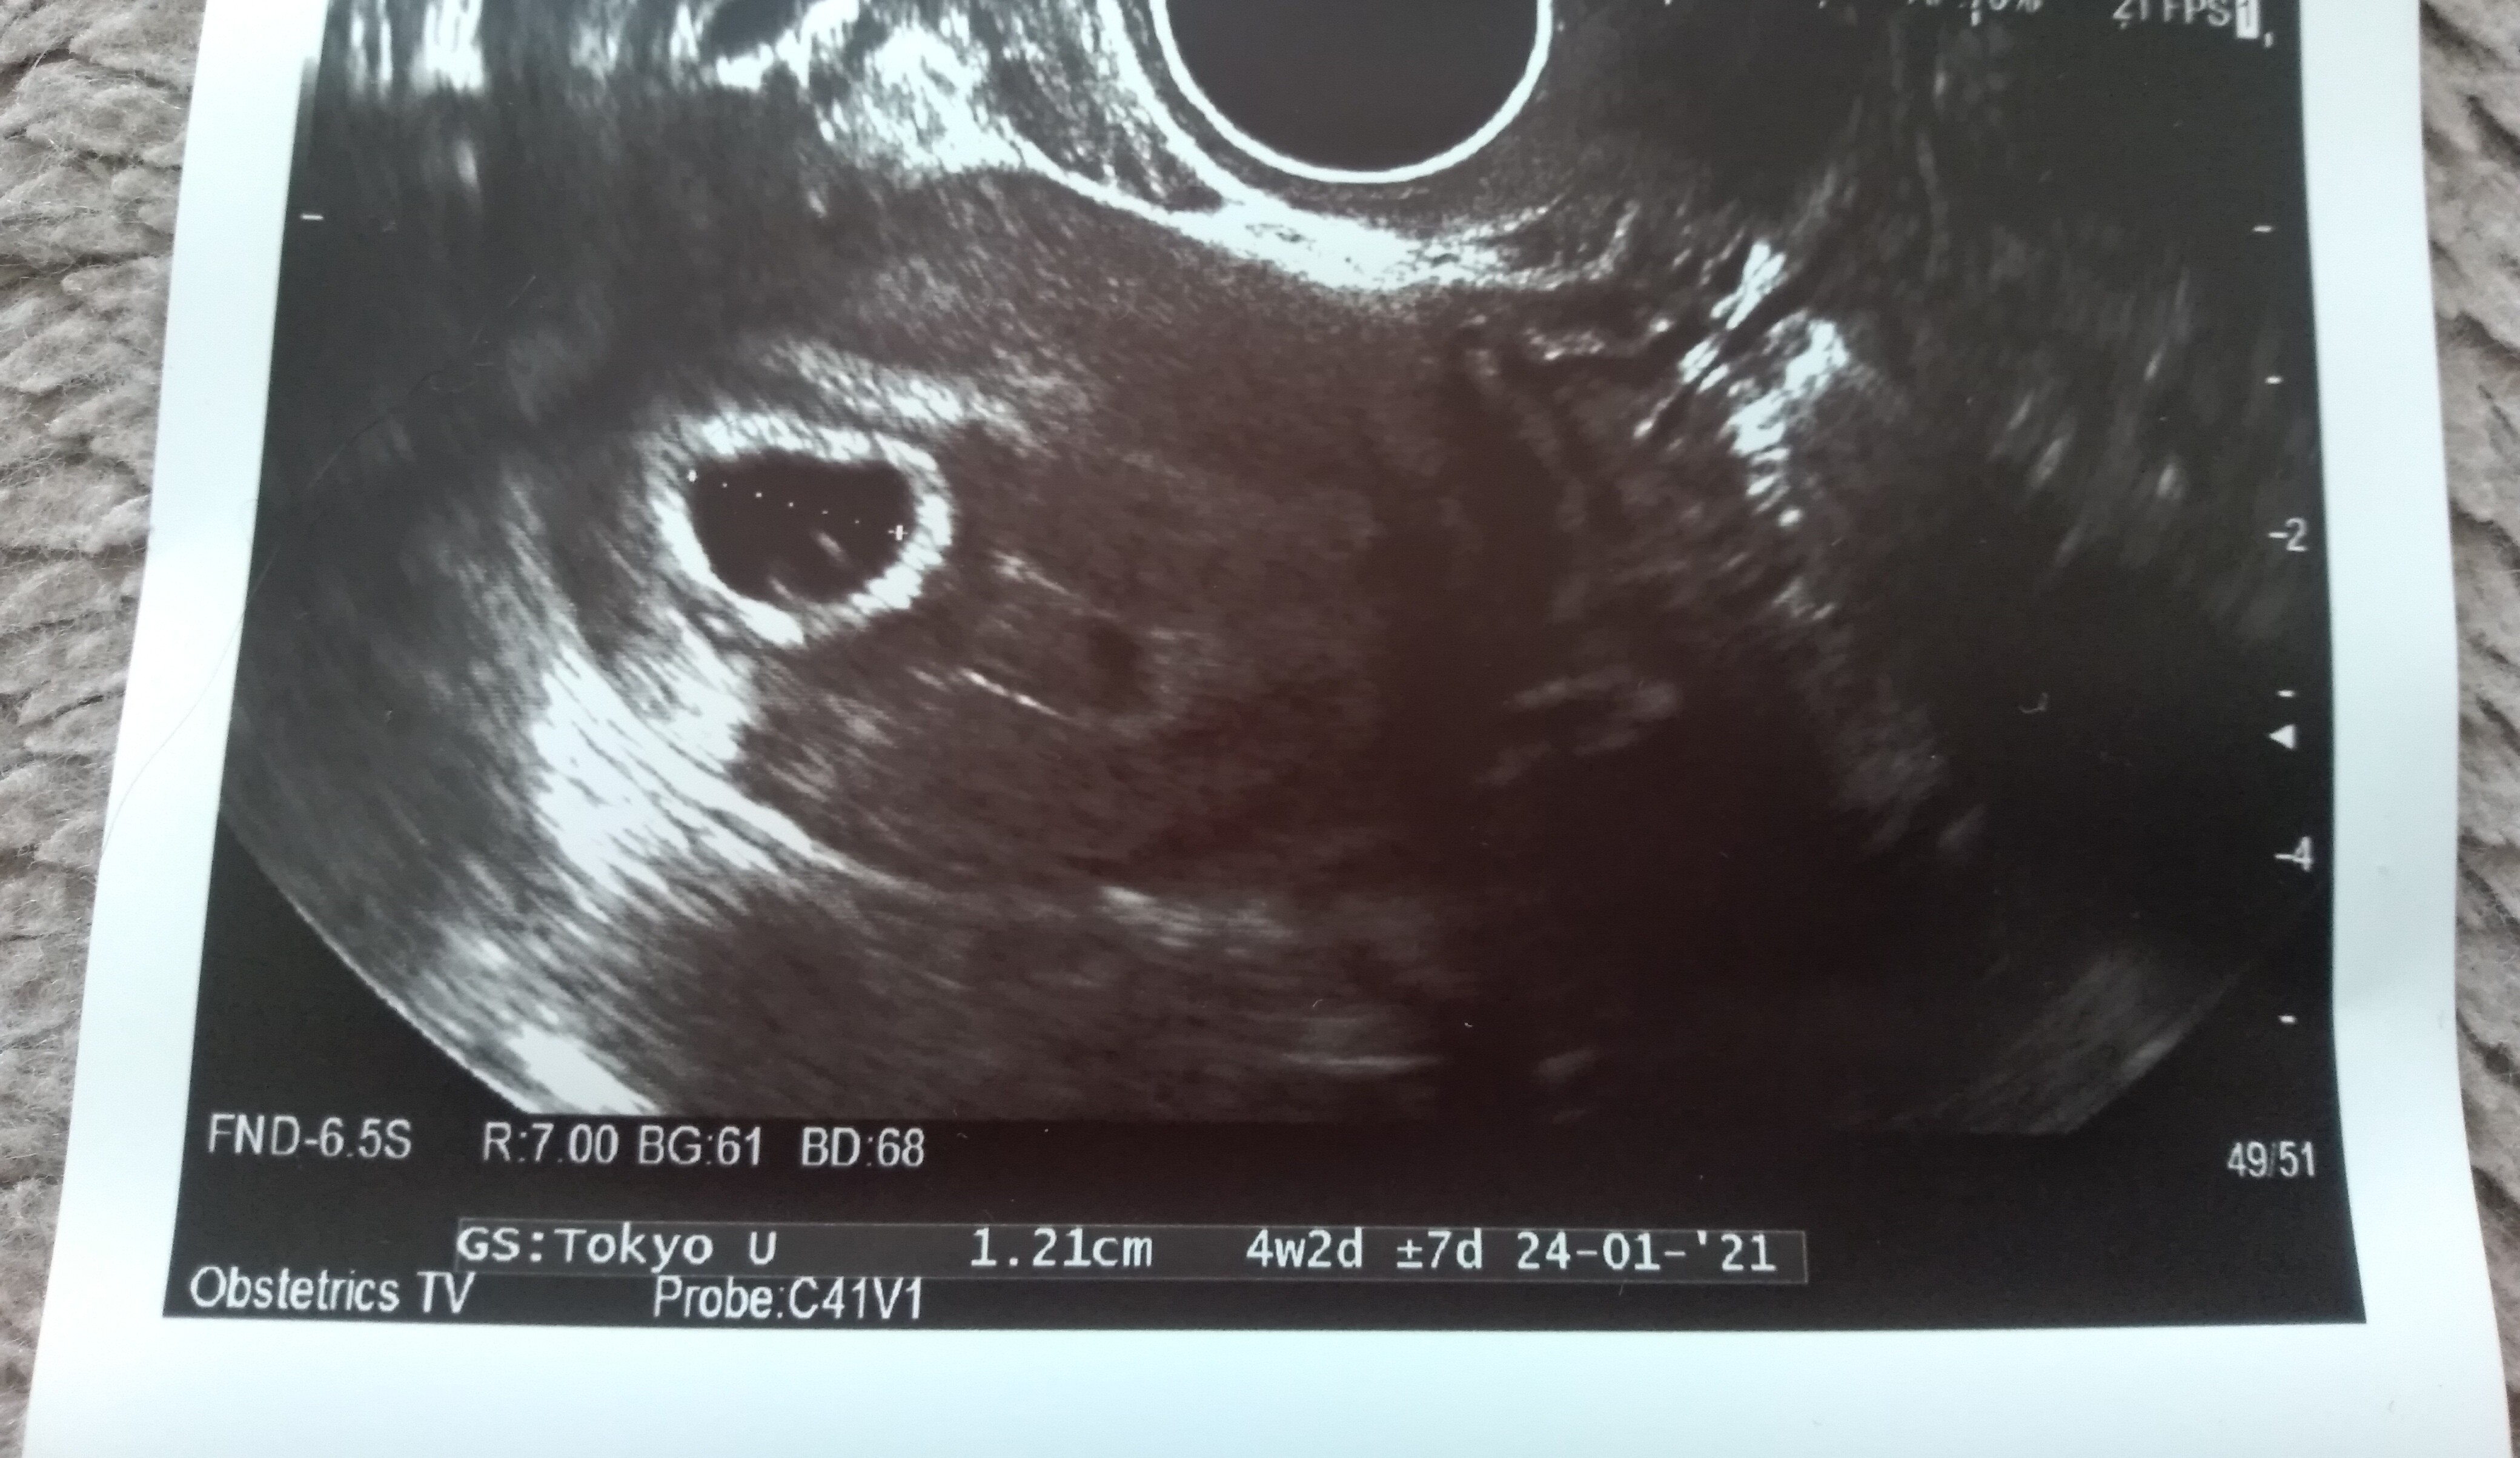

powiedziała, że pęcherzyk ciążowy jest za mały na swój wiek. Ma 1,21 cm. Według aplikacji dziś 6+1

Jednak ciąża jakby jest młodsza o 2 tyg - usg pokazuje 4+2